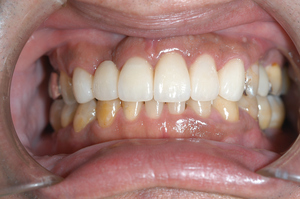

歯周病を改善することは、歯をキレイにすることだけでなく、様々な合併症のリスクを抑制して、健康な体を取り戻します。

![img03[1]_コピー](/materials/162264278603901.png?_=1622642786)